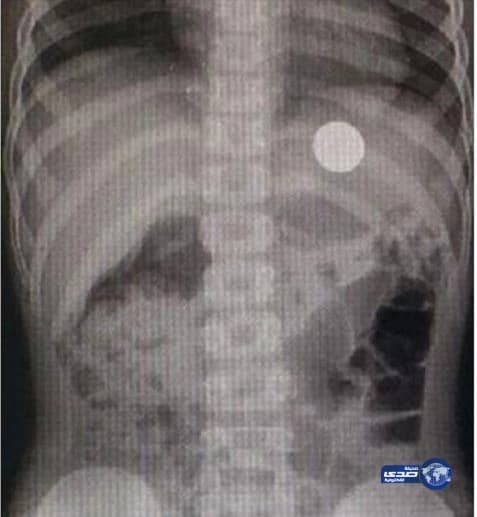

نجح فريق طبي بوحدة مناظير الجهاز الهضمي وقسم جراحة الأطفال في مستشفى الولادة والأطفال في بريدة في استخراج عملة معدنية من صدر طفل يبلغ من العمر 7 سنوات. وأوضح قائد الفريق، رئيس قسم وحدة مناظير الجهاز الهضمي بالمستشفى الدكتور عبدالعزيز عبيد الحربي، أن العملية أجريت للطفل بنجاح، وهو بصحة جيدة. وأضاف أن هذه العملية تعد الأولى التي تجرى بالمنظار، والمستشفى يعمل على تطوير جراحات المناظير والجهاز الهضمي، مما يسهم في تقديم أفضل خدمة علاجية للمرضى. وشدد على ضرورة الاهتمام بمتابعة الأطفال، وما يضعون في أفواههم حتى لا يتعرضوا للاختناق أو مضاعفات العمليات نتيجة استخراجها.